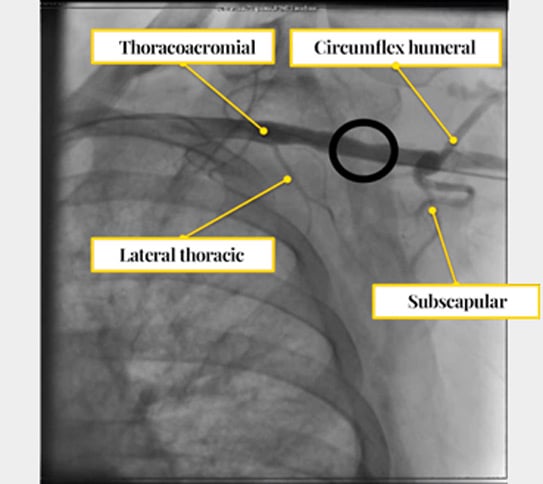

Step 2: set up a “backup safety channel” before accessing the axillary artery

- Insert a 6–7Fr sheath in the ipsilateral radial artery or femoral artery (we prefer a 45-cm-long 7 Fr sheath via the femoral artery) for control angiography and bailout interventions (balloon control or covered stent if required) (Figure 6).

- The backup wire is usually rolled up and covered with a tarp to prevent it from getting damaged.

- Define a rescue wire strategy from the outset; don’t commit to irreversible closure steps without a bailout plan.

Figure 6: 7Fr sheath in the femoral artery (for control angiography and bailout interventions); 6Fr-sheath for PMK